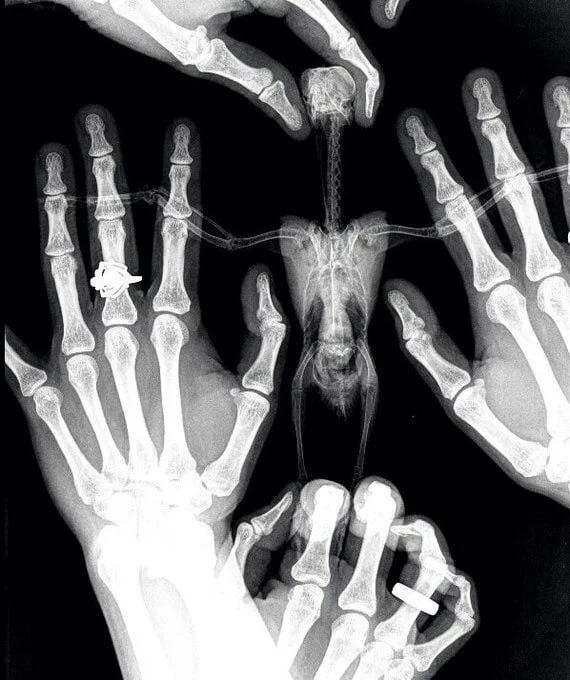

6. Для тех, кто не видел птичий рентген